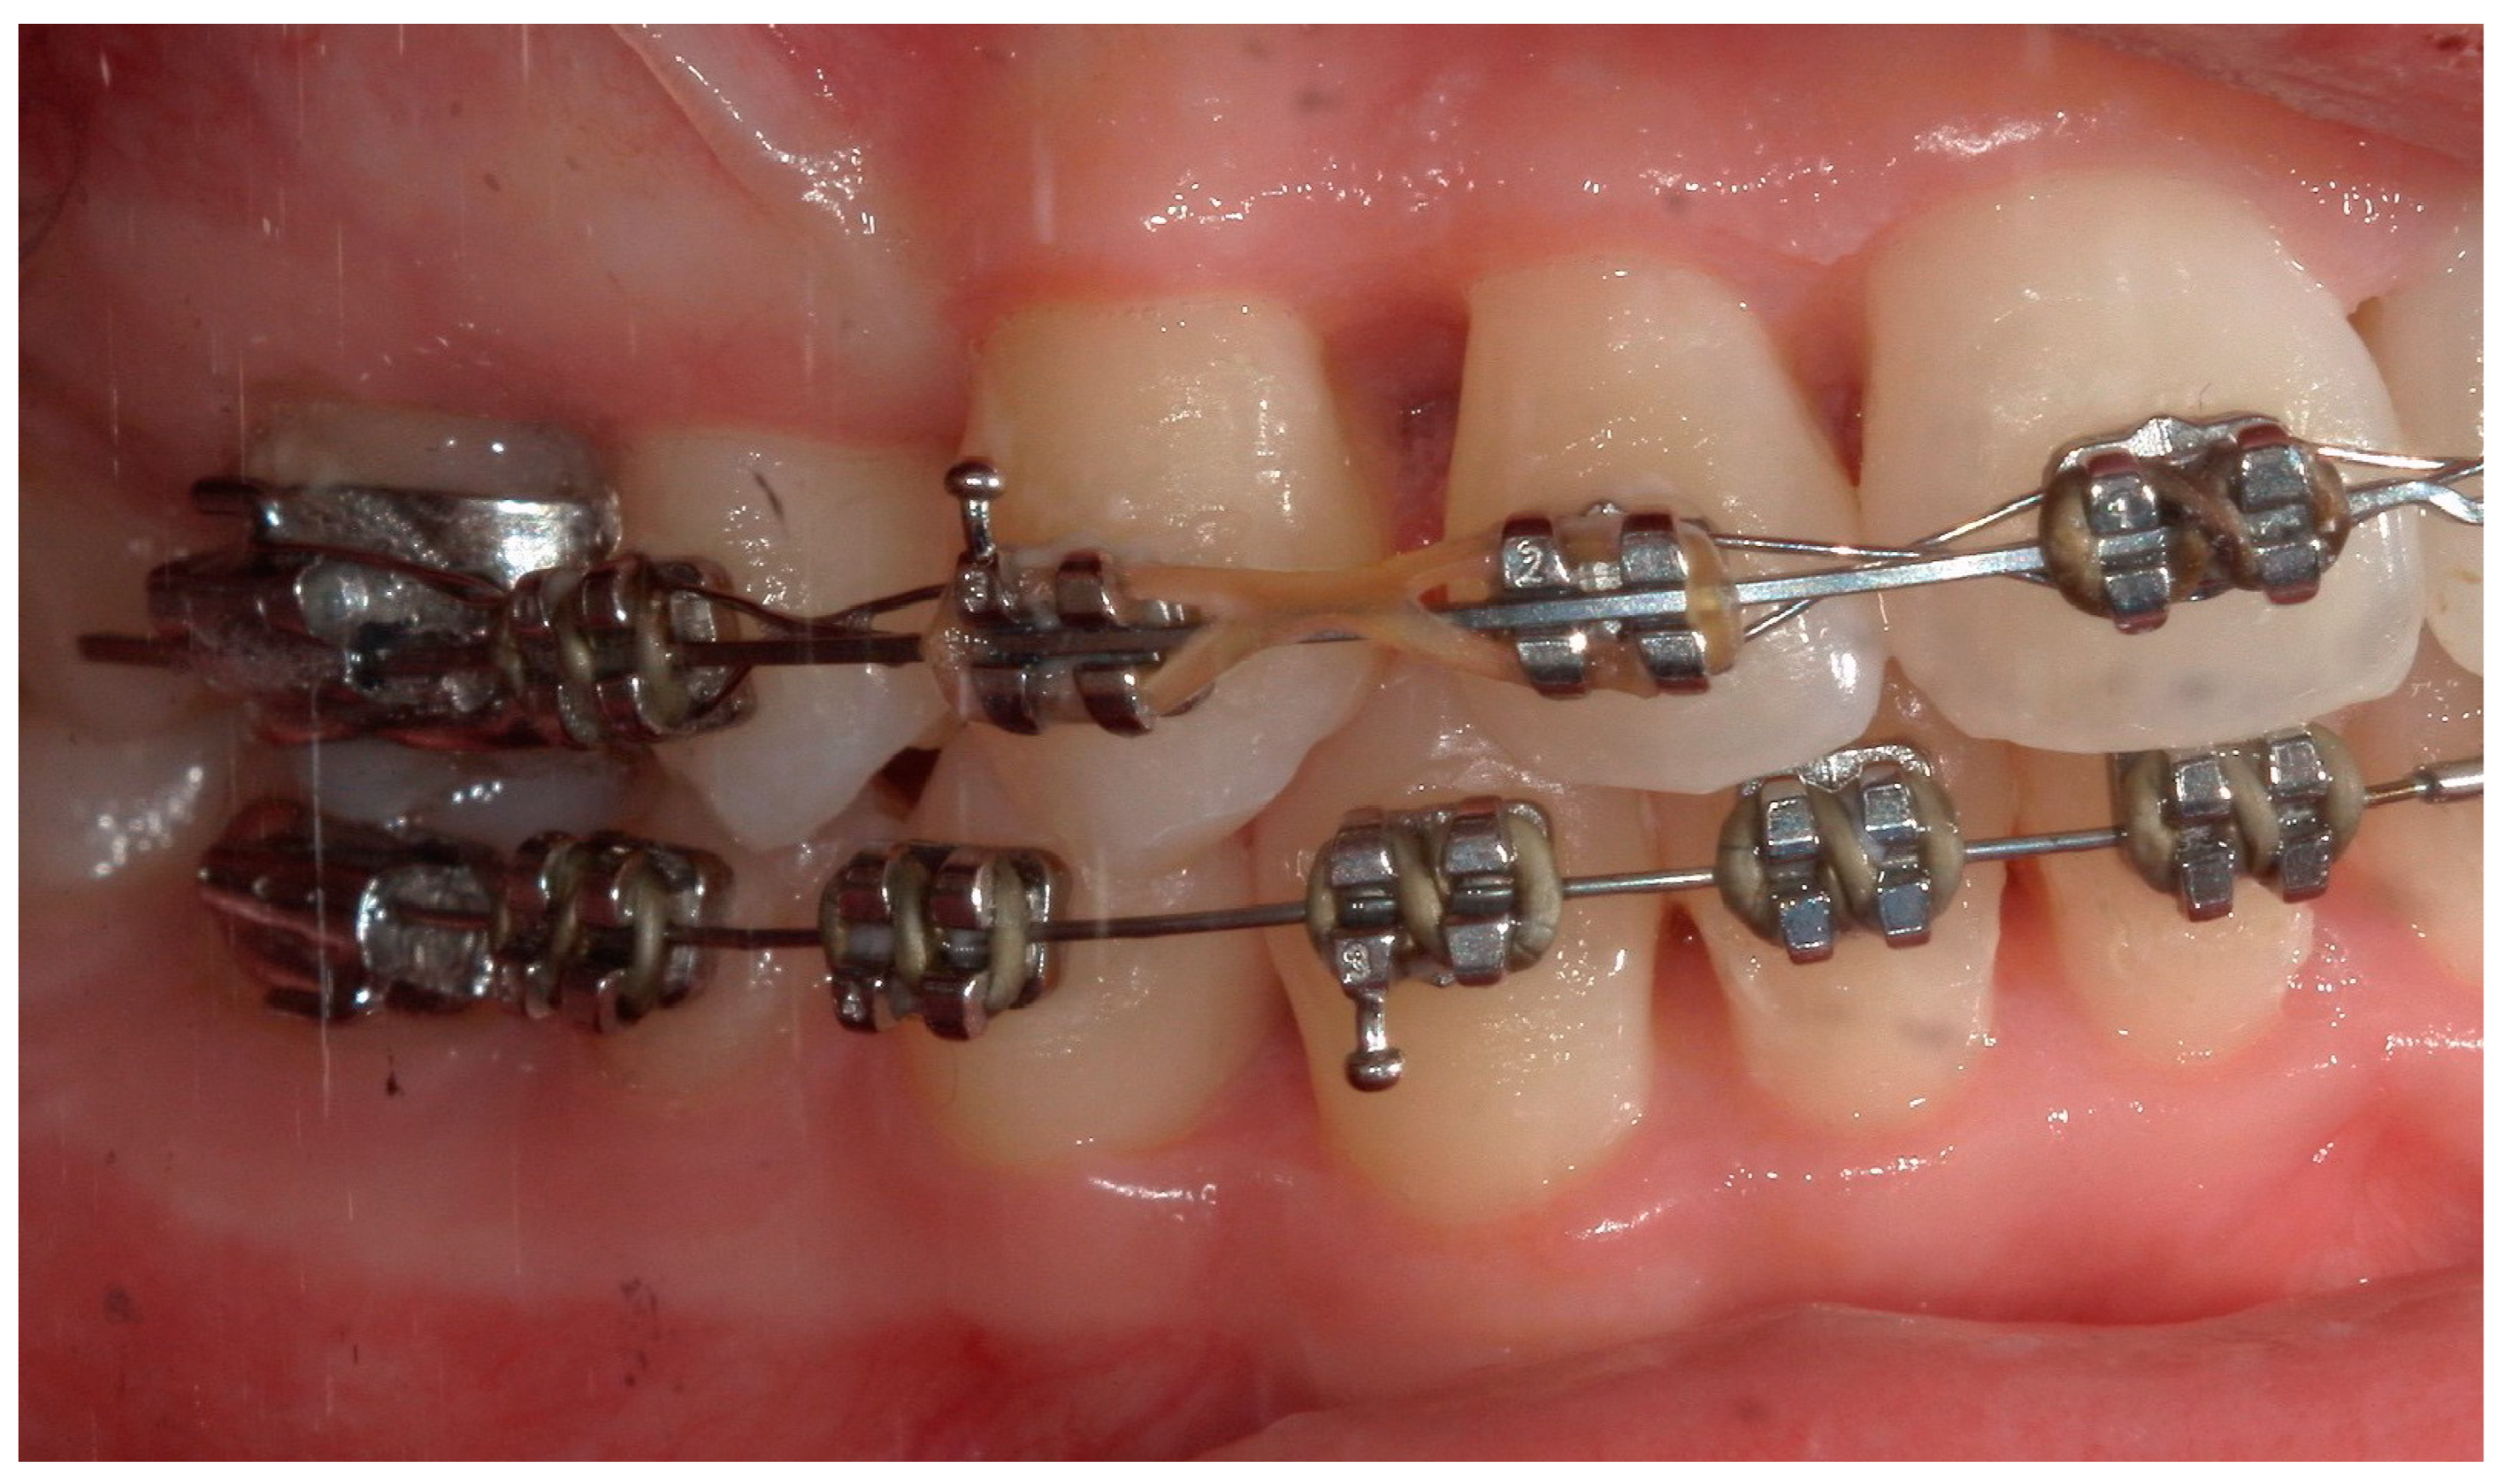

4.1. Case 1

4.2. Case 2